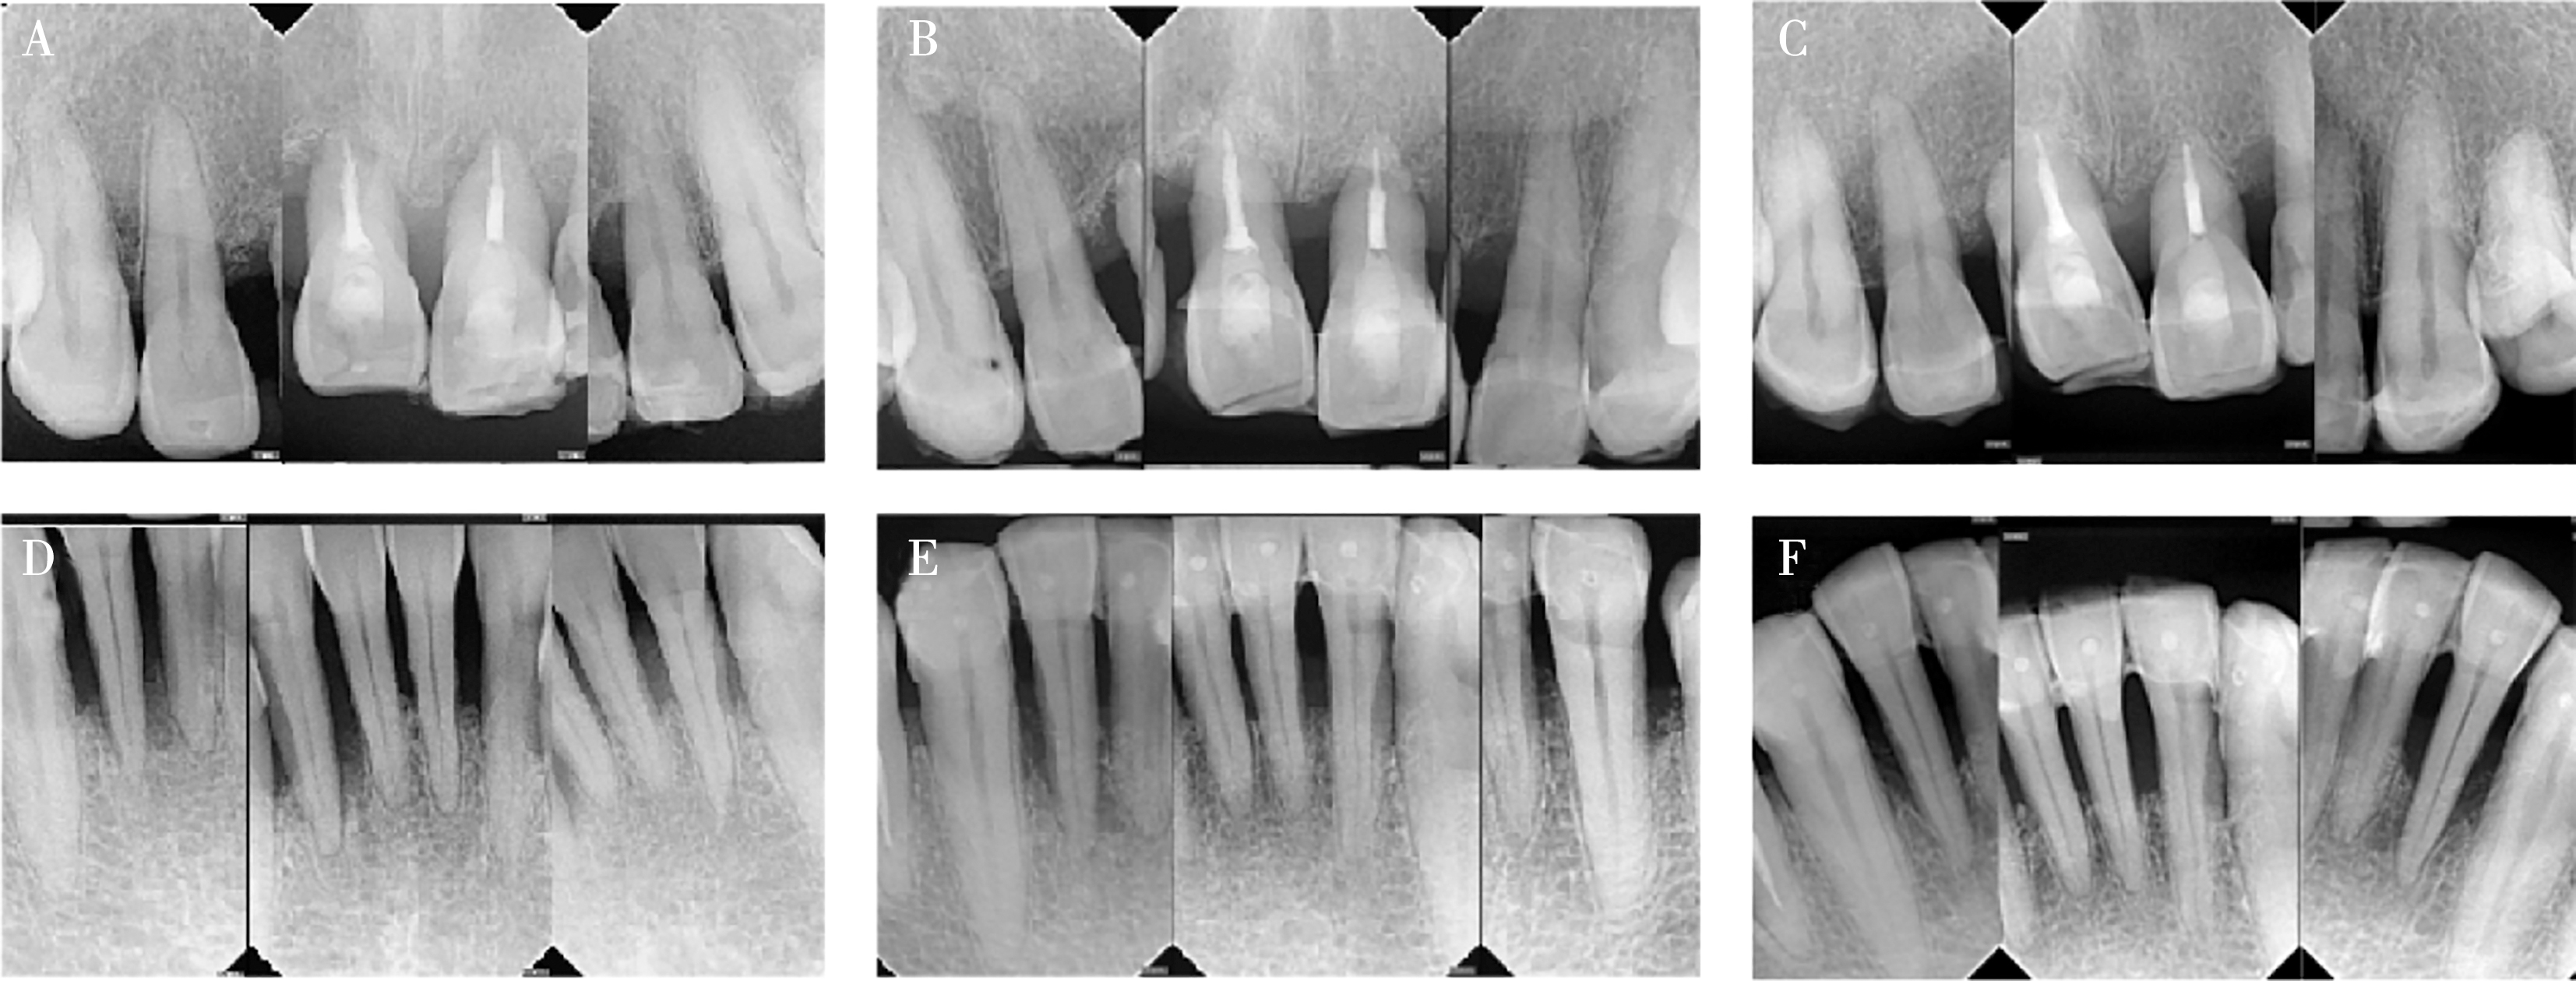

Zhang CR, Liu Q, Yang JW, et al. A digital technique for splinting periodontally compromised mobile teeth in the mandibular anterior region[J]. J Prosthet Dent, 2021, 125(4): 560-563.

Liu YC, Bai SZ, Zhong S, et al. Digital workflow for periodontal splinting with a guided device[J]. J Esthet Restor Dent, 2023, 35(4): 621-624.